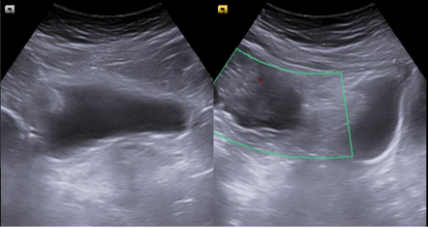

Compresión extrínseca de la vejiga por tumoración mixta solidoquística que proceden de zona anexial derecha, en zona superior y lateral derecha.

La ecografía abdominal es una herramienta muy útil para el Médico de Familia y permite adelantar el tiempo diagnóstico y el inicio del tratamiento de la patología subyacente. En este caso, gracias a la realización de una ecografía clínica en el centro de salud, se pudo objetivar una masa anexial derecha, causante de la sintomatología, y de esta forma iniciar el tratamiento de una forma precoz.